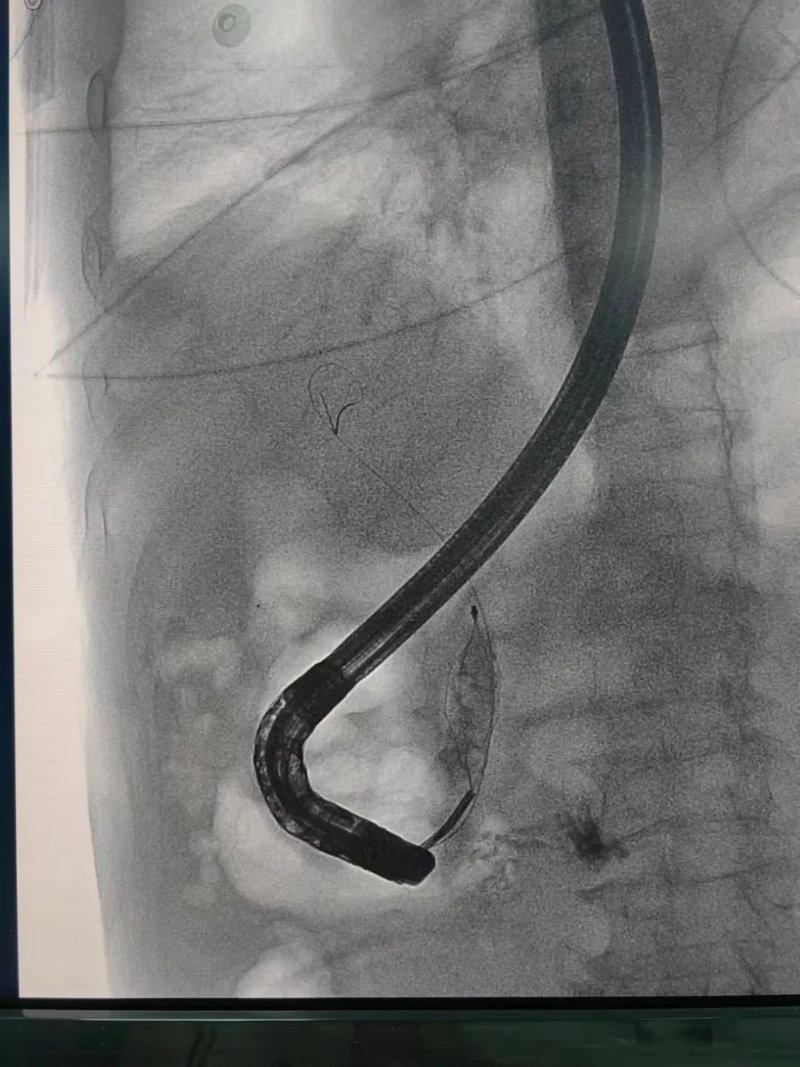

73毫米“炸彈”藏腹中!我院微創手術巧拆除解危機

膽管結石、阻塞性黃疸、胰腺炎……這些疾病不僅讓人痛苦,還可能危及生命。過去,治療這類疾病往往需要開腹手術,創傷大、恢復慢。而現在,經內鏡逆行胰膽管造影術(ERCP) 作為一種先進的微創技術,已經成為膽胰疾病診斷和治療的重要手段。

它無需開刀,僅通過內鏡就能精準處理膽管和胰管的問題,大大減輕患者痛苦,縮短恢復時間。那么,ERCP究竟能解決哪些問題?它的優勢又在哪里?讓我們一起來了解。

什么是ERCP

經內鏡逆行胰膽管造影術(以下簡稱ERCP)是治療膽管結石的首選方法,ERCP屬于介入和微創手術,可以有效減少傳統手術對患者身體的創傷,能快速緩解臨床癥狀,降低相應并發癥的發生,改善肝功能,促進患者康復、減少圍術期應激,縮短住院時間,是項較安全、直觀、可靠的治療手段,對肝膽、胰疾病有較高的診斷和治療價值。

文章配圖

ERCP是經口內鏡膽道治療技術。是國際公認的膽管胰腺系統疾病診斷的金標準,是確診膽管結石的最佳方法。在ERCP基礎上,可以同時進行膽總管結石取石術、Oddis括約肌切開術、膽總管支架植入術、鼻膽汁引流術等微創手術,對膽總管結石等疾病進行安全、快速、有效的治療。